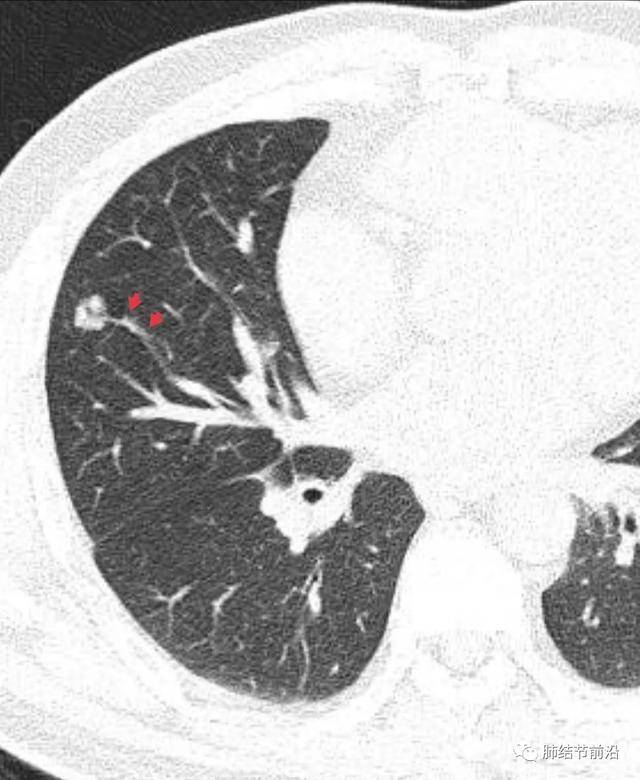

什么是肺結(jié)節(jié)呢?肺結(jié)節(jié)是指肺部出現(xiàn)的一種直徑小于或等于3厘米的圓形或近似圓形的病灶,大多數(shù)肺結(jié)節(jié)是良性的,只有一小部分可能是惡性的。

診斷肺結(jié)節(jié)主要依賴于醫(yī)學影像技術(shù),如X光、CT等,醫(yī)生會根據(jù)患者的病史、體征和影像學表現(xiàn)進行綜合判斷,對于疑似惡性的結(jié)節(jié),可能需要進行進一步的檢查,如活檢等。